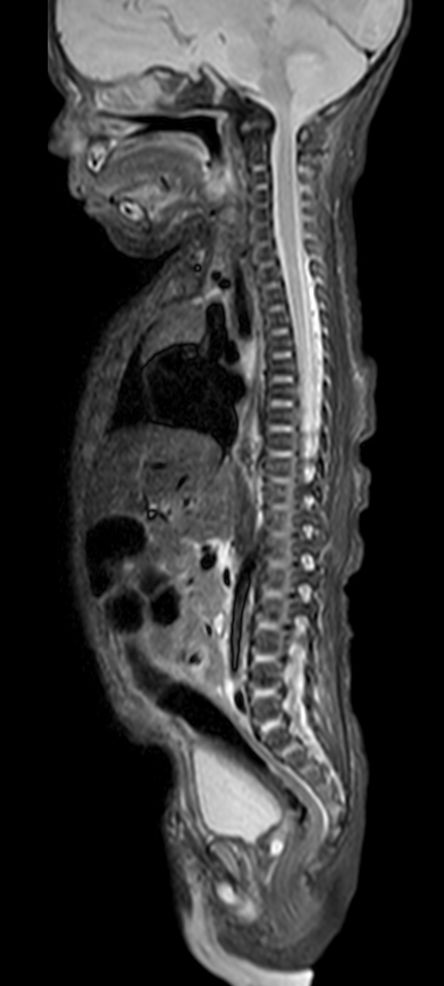

Pediatric Total Spine with spina bifida

Neonatal patient, 5 days old, with spina bifida